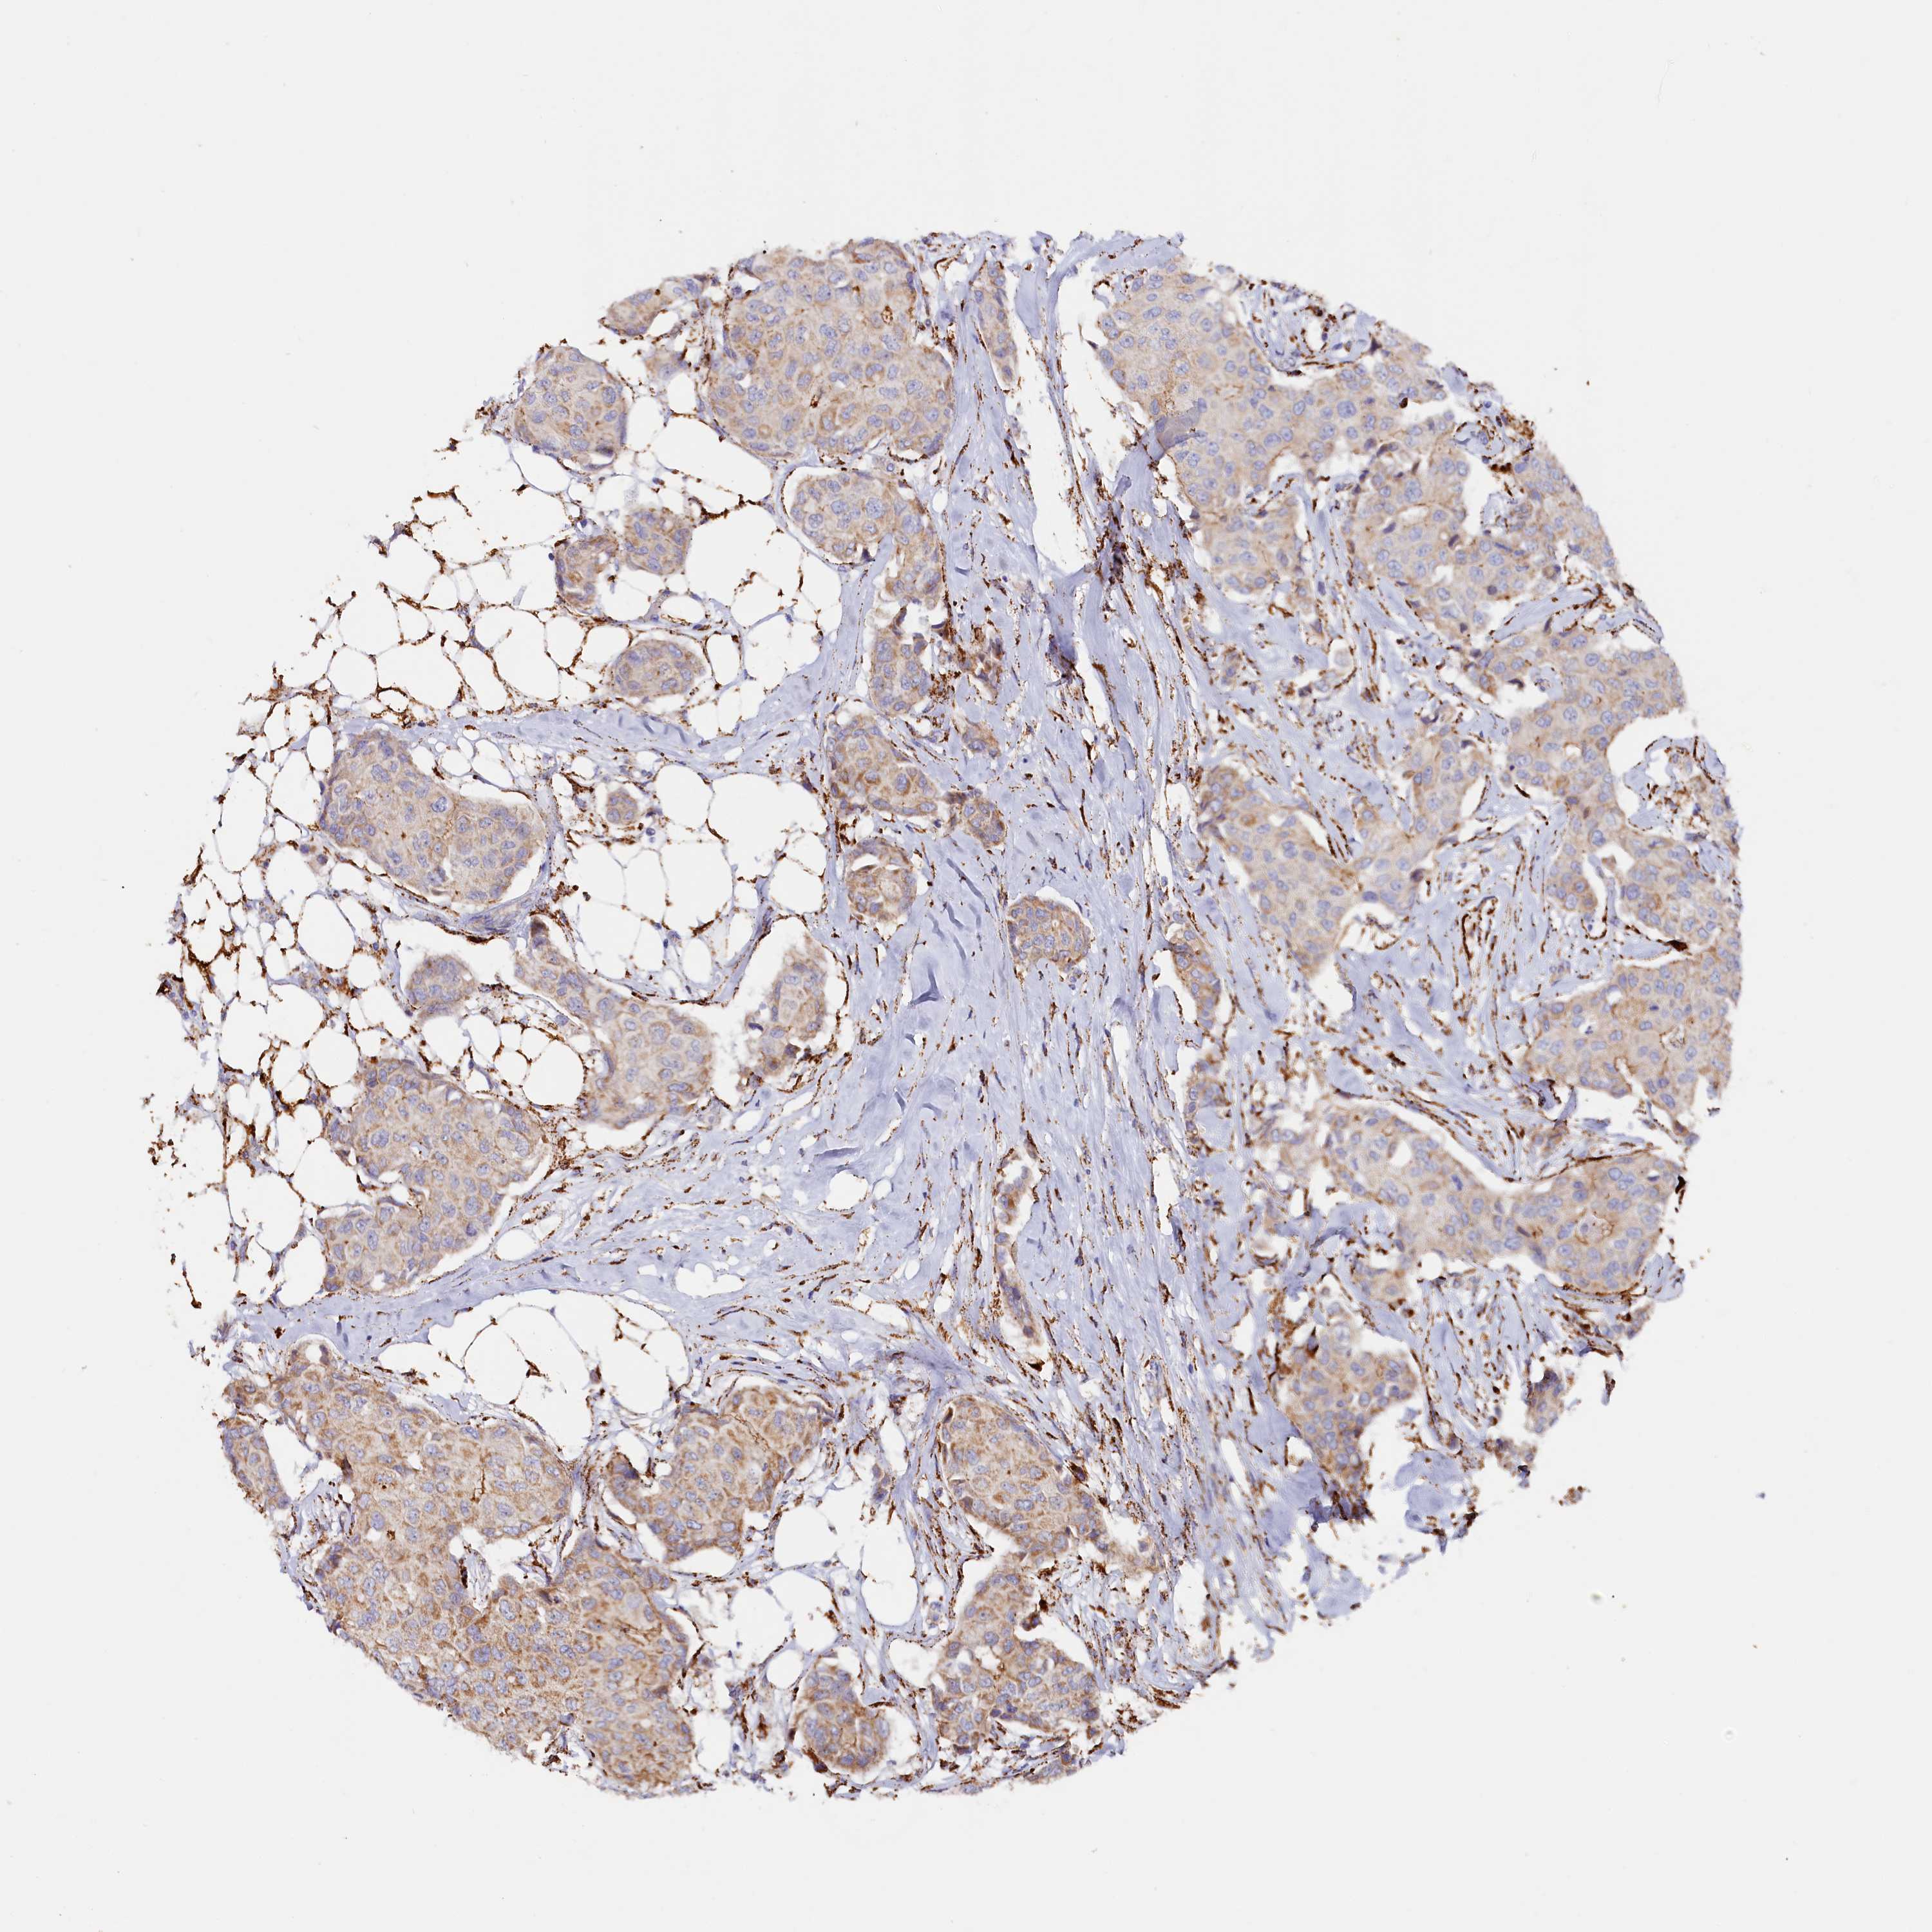

CANCER BREAST CANCER Show tissue menu

BRCA TCGA BRCA VALIDATION PROTEIN EXPRESSION